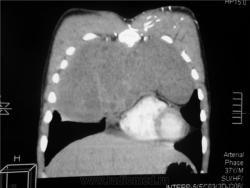

КТ август 2009.

Интенсивное, однородное затемнение в средних отделах справа, слева норма - мною был заподозрен м/долевой плеврит, пациент был направлен в областной центр торакальной хирургии. Затем онкодиспансер, затем институт рака в Киеве. Результат гистологии тератобластома средостения. 2 курса химиотерапии контрольное КТ в октябре - отрицательная динамика.

Массивное неоднородное мягкотканное новообразование, исходящее из верхней или средней трети переднего средостения, оттесняет крупные сосуды вправо и кзади. По локализации должна быть злокачественная тимома. Хотя и лимфому наверное, не стоит отбрасывать, Ходжкинская маловероятна.